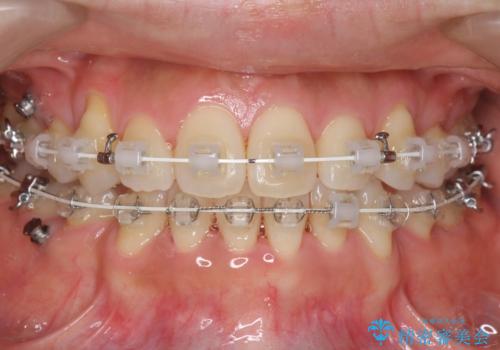

- 矯正装置

- ワイヤー矯正

小臼歯抜歯を行い、ワイヤー矯正を行いました。